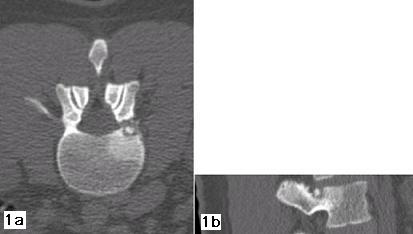

Figura 3 - Il controllo con RM, eseguito dopo 15 mesi dalla procedura, non fa più apprezzare l'osteoma osteoide; le strutture foraminali sono indenni; sono ancora presenti modesti fenomeni riparativi nella sede della termoablazione.